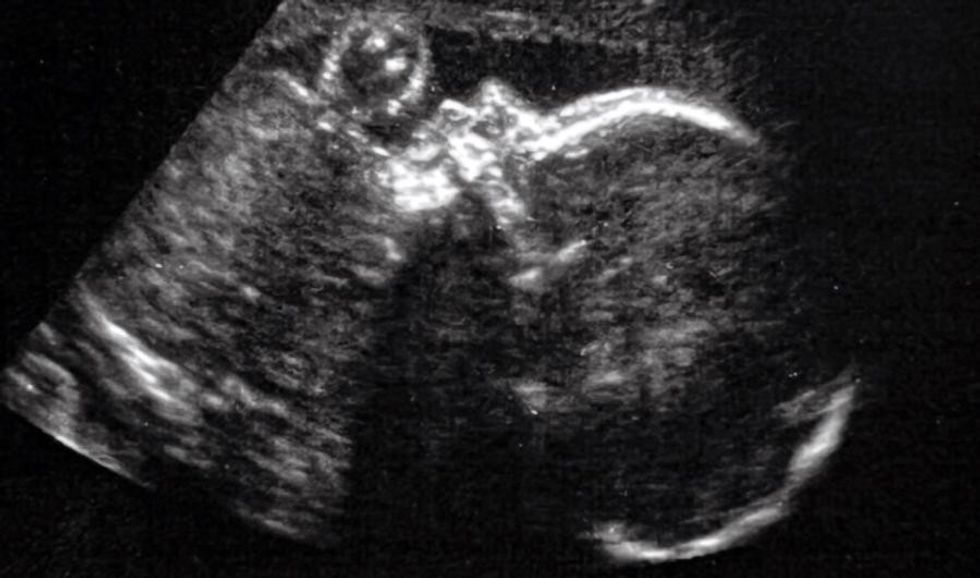

After that ultrasound, Kenyatta’s doctor sat her down and told her that she had seen a malformation. The scan showed that the baby’s heart was abnormally large. “She shared with me that something wasn’t right in terms of the baby’s brain,” Kenyatta said.

That something turned out to be a vein of Galen malformation, or VOGM.

It’s a rare blood vessel abnormality in the brain that causes a high-pressure rush of blood into the veins. With VOGM, the heart works harder to get blood to all the parts of the body, which can lead to congestive heart failure in infants. Brain injuries arise from blood in the infant’s brain not draining adequately.